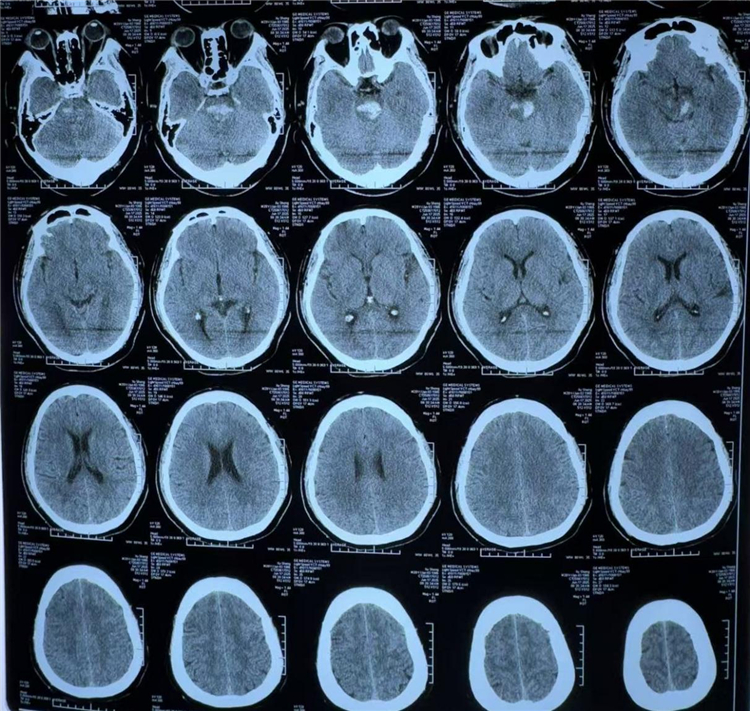

术前CT:脑干出血

日前,39岁的吴先生(化名)突发头晕后意识丧失,被紧急送至长沙泰和医院。入院时,患者已陷入昏迷,自主呼吸停止,瞳孔缩小且光反射消失。经紧急气管插管维持呼吸,并完成头部CT检查,确诊为脑干出血,出血量约8毫升,病情十分危重。